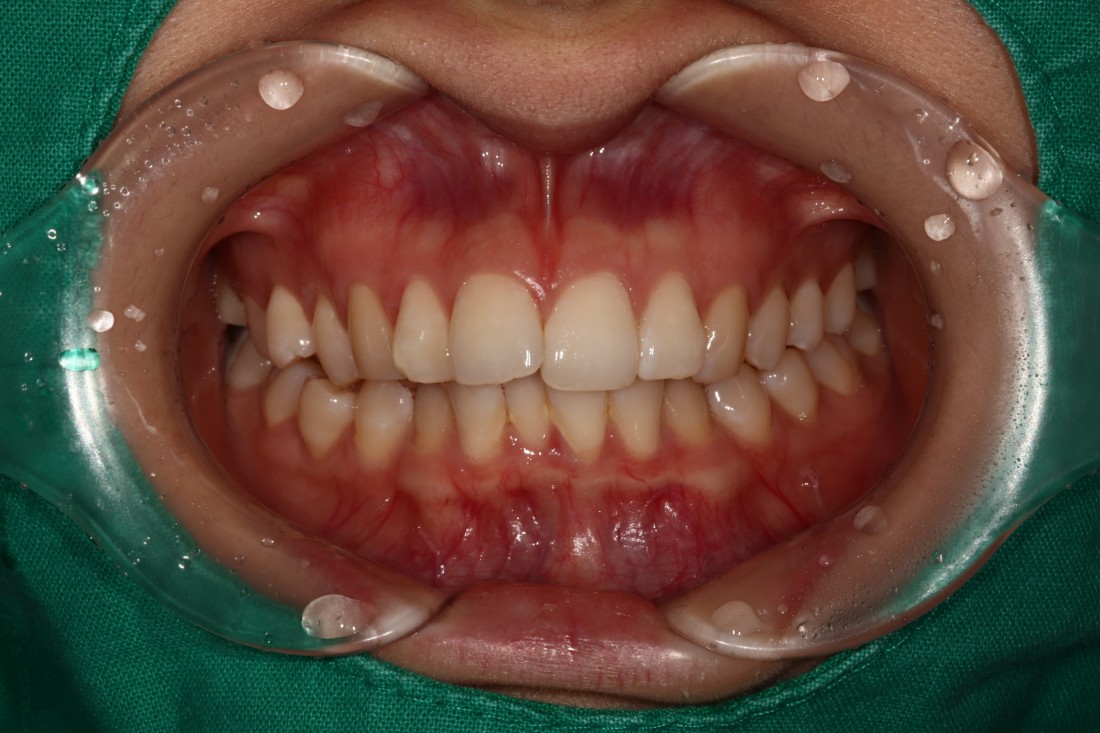

광주 교정치과

충치치료 + 치아교정 동시 케이스

광주 교정치과 추천하는 이유는

전문의 충치치료까지 동시에 가능하여

토탈 구강건강 관리를 받으실 수 있기 때문입니다.